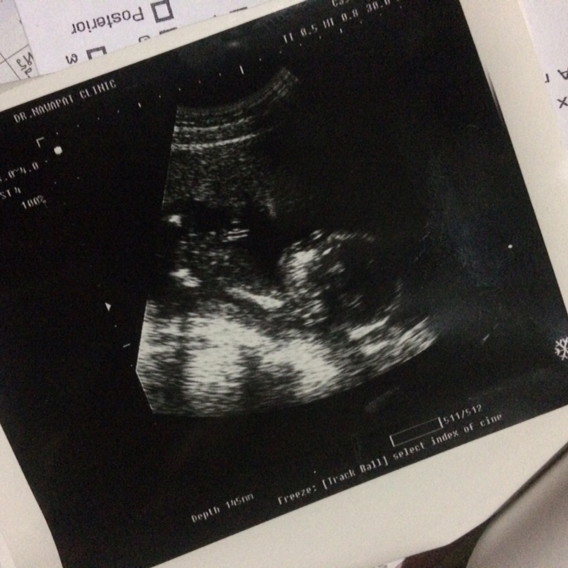

5เดือนค่ะ